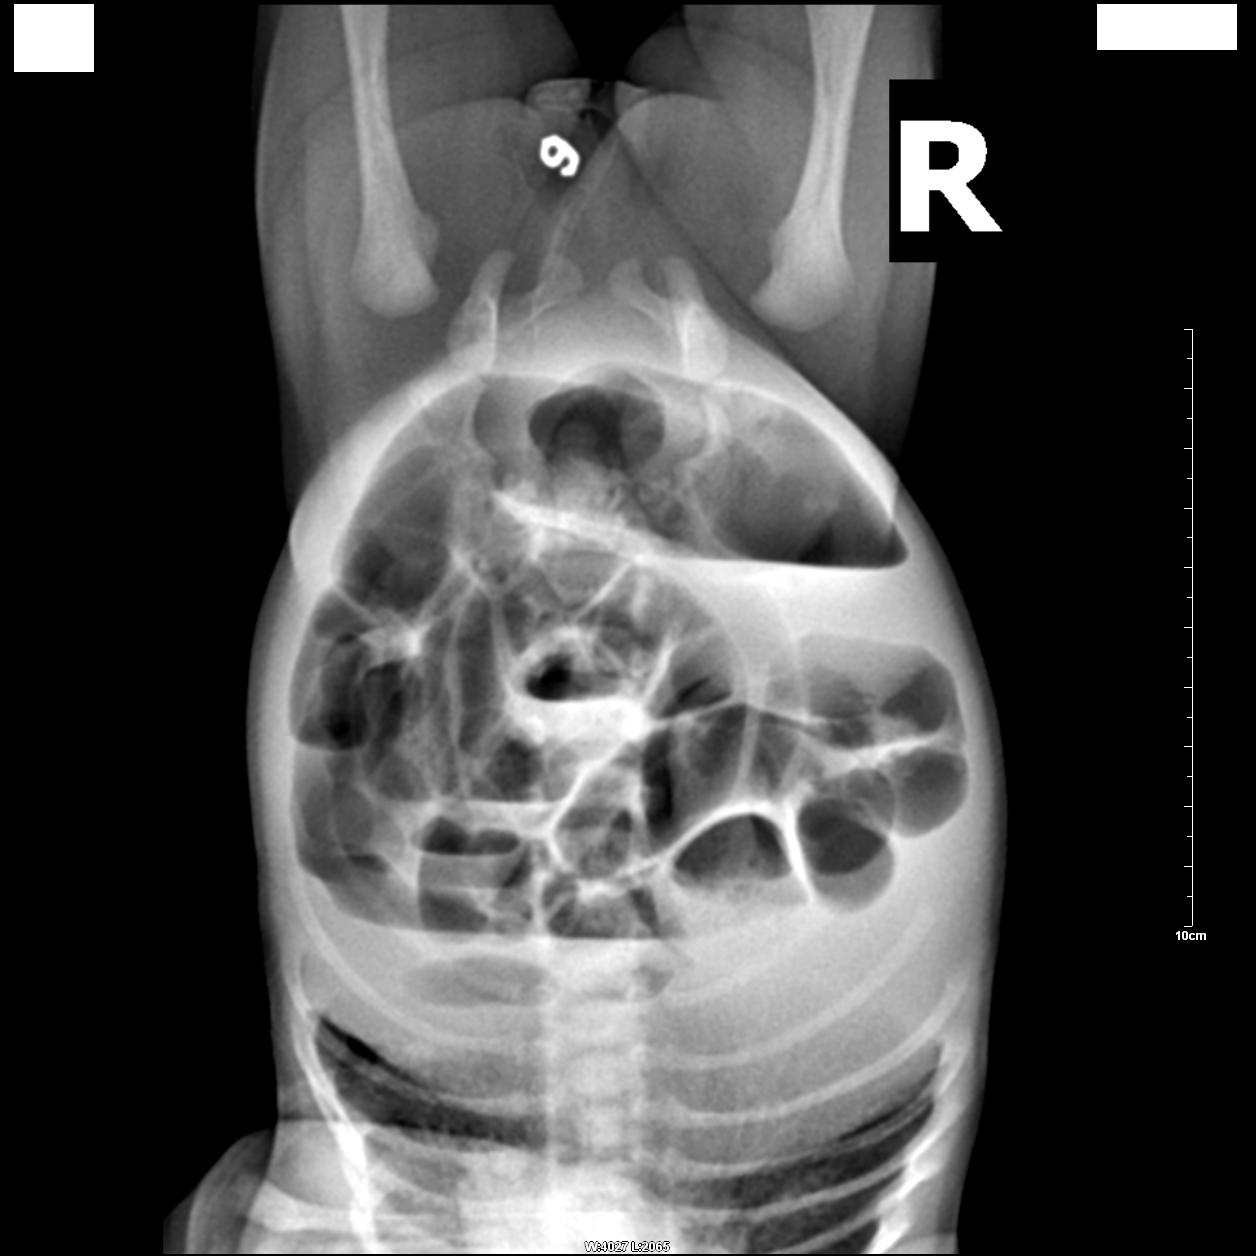

标题: PED0943:考虑先天性肛门闭锁。 [打印本页]

标题: PED0943:考虑先天性肛门闭锁。

患者,女,生后7天无排便。

肛门部位标记,腹部倒立正侧位:

典型!肌性闭锁。

看到26楼还是没有一个人去具体诊断,如果临床要你去诊断\"肌性闭锁\",那他们可以不拍片了.术前临床需要什么?这才是照片的目的,我们需要告诉临床,闭锁是高位还是低位,还是中位,那么具体到胶片上就是找pc线了.一味的同意,一味的支持,一味的典型,能给\"临床大夫一做直肠指诊不就得了\"\"做个直肠镜就可以\"回帖者什么好处?如果没人指点,他们永远在迷宫里.

相信大家都能明确诊断,希望回帖品质再提高点,让更多初学者在这里有更多收获.